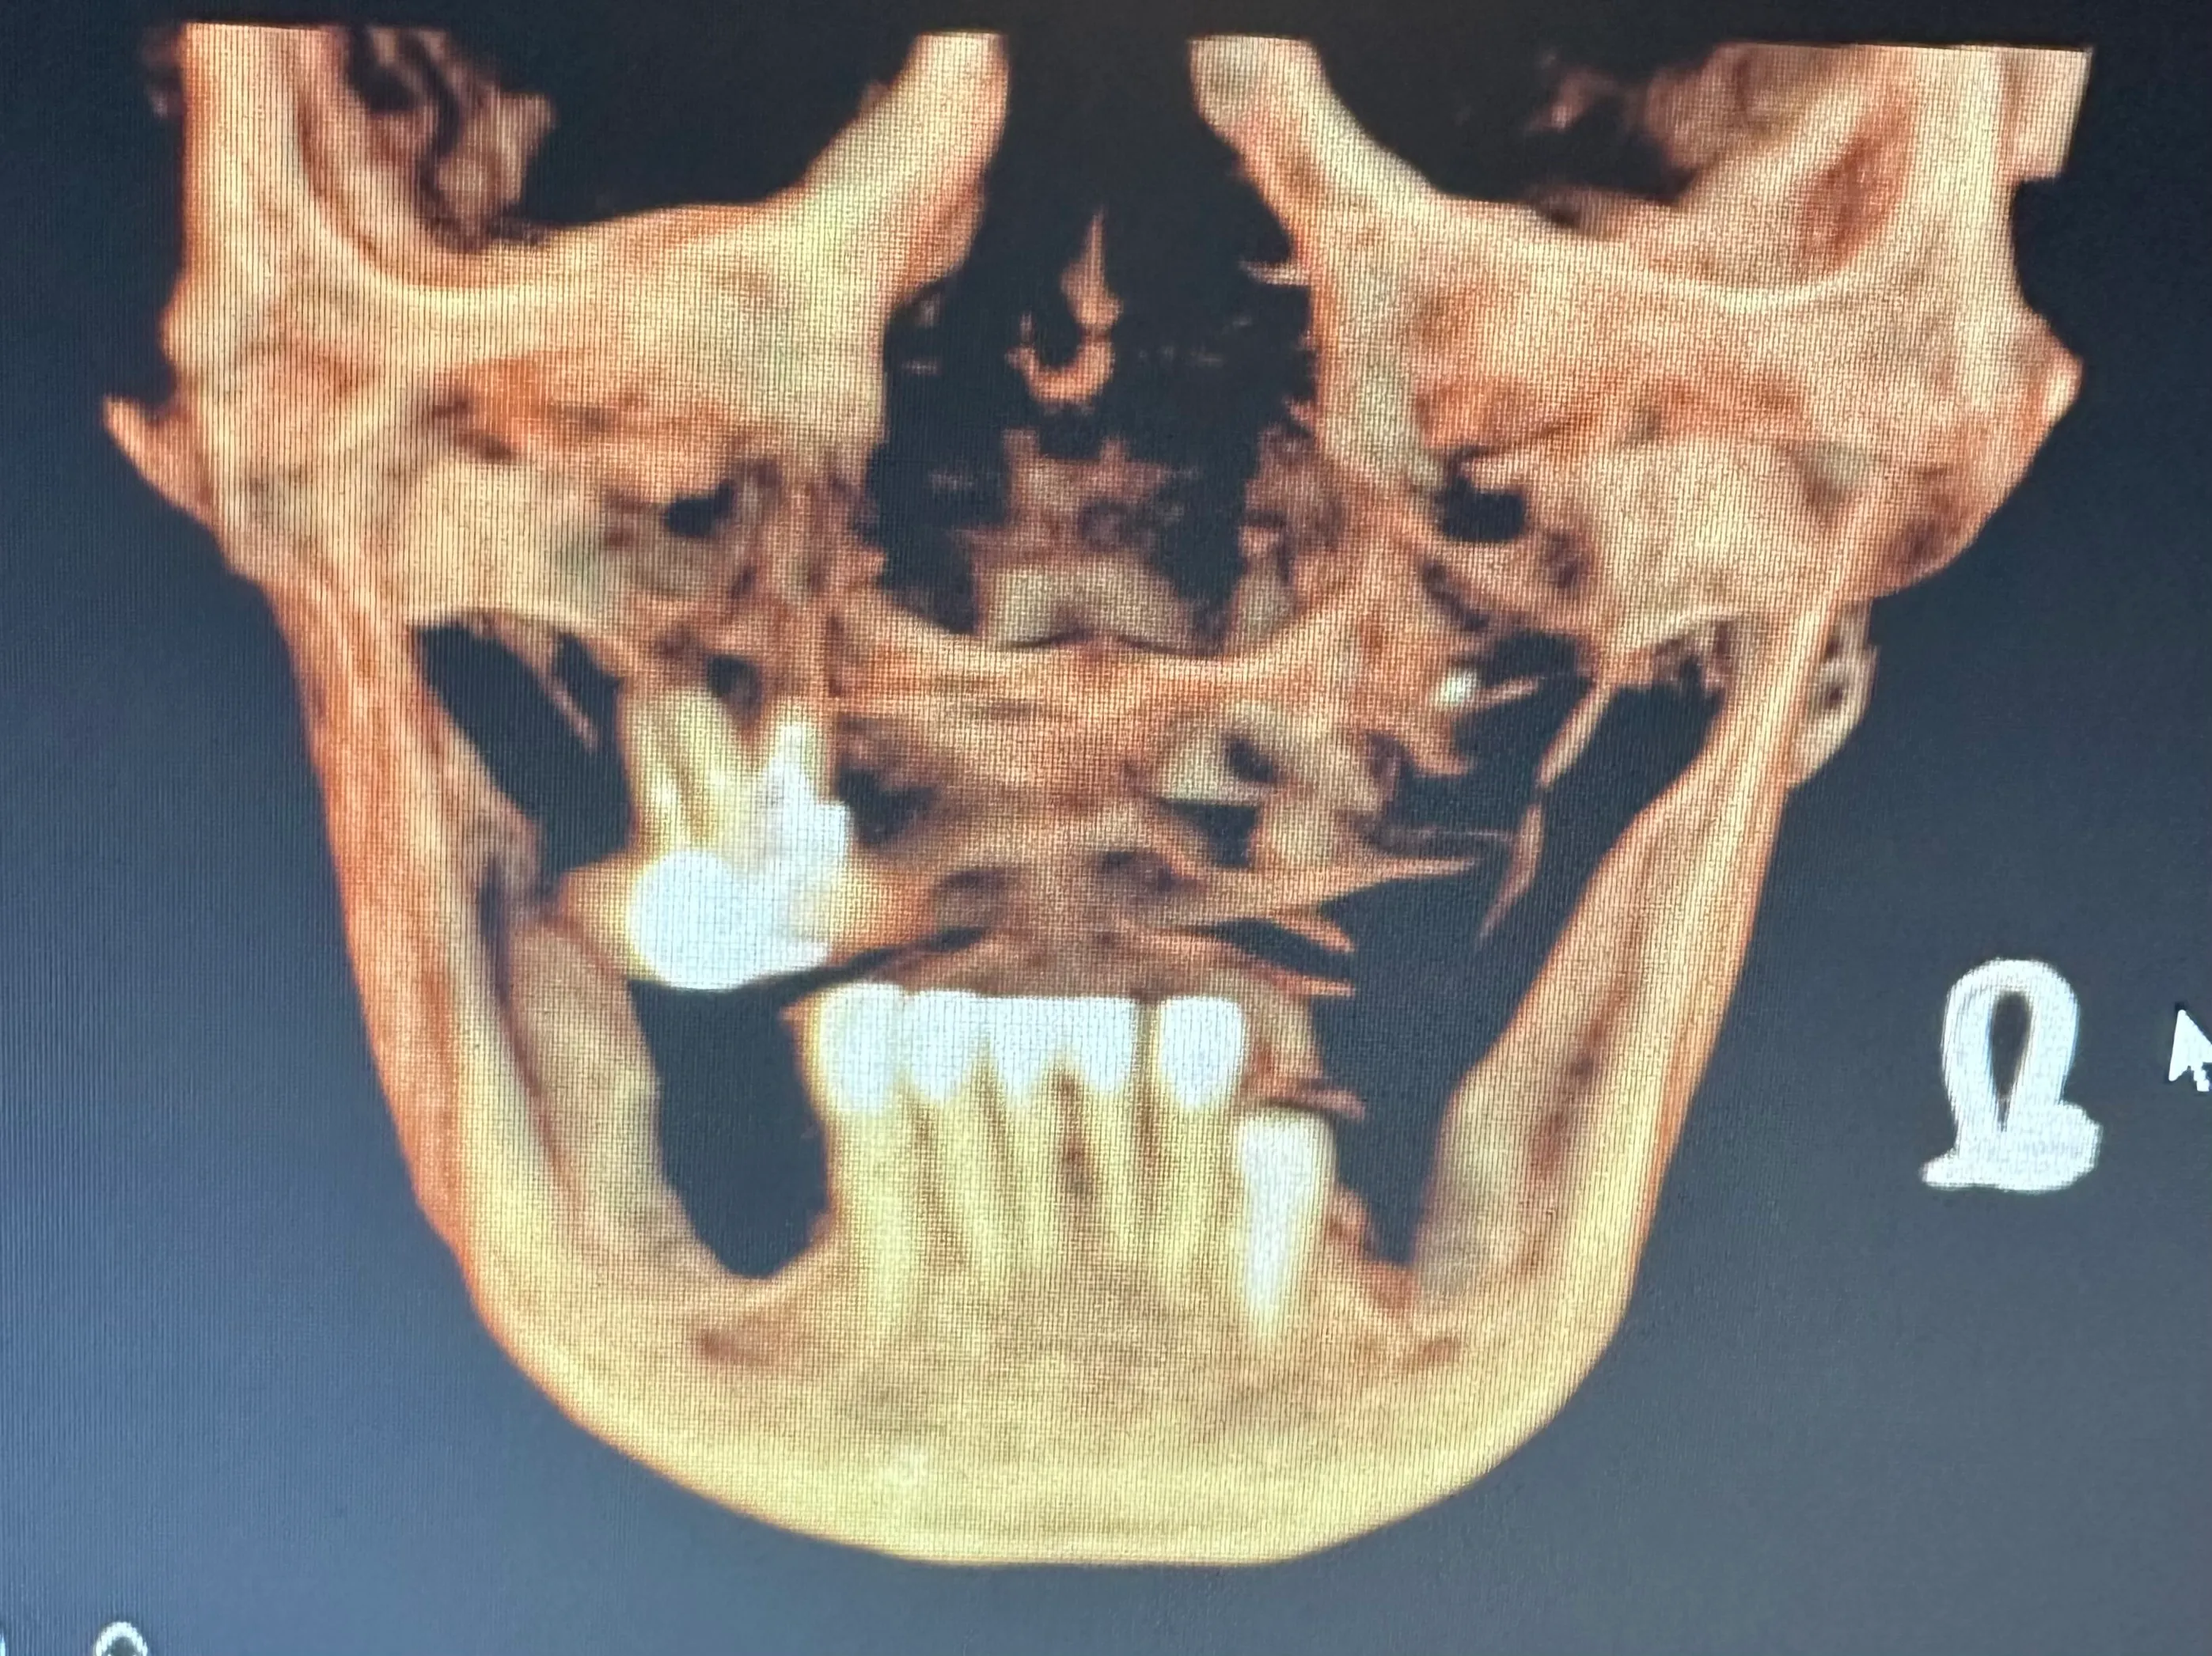

X-ray image of a jaw with dental implants and surgical plates, highlighting the alignment of teeth and orthopedic hardware.

Normally, implants are placed in the maxilla to replace missing teeth in the upper jaw. However, some patients have such severe bone loss that there isn’t enough to place an implant safely. In this case, longer implant screws can be used to reach the cheekbones, which are used as an anchor instead.

Zygomatic dental implants are sometimes called “rescue implants” because they can help patients achieve a fully functional bite and aesthetically pleasing smile when bone grafting isn’t possible.